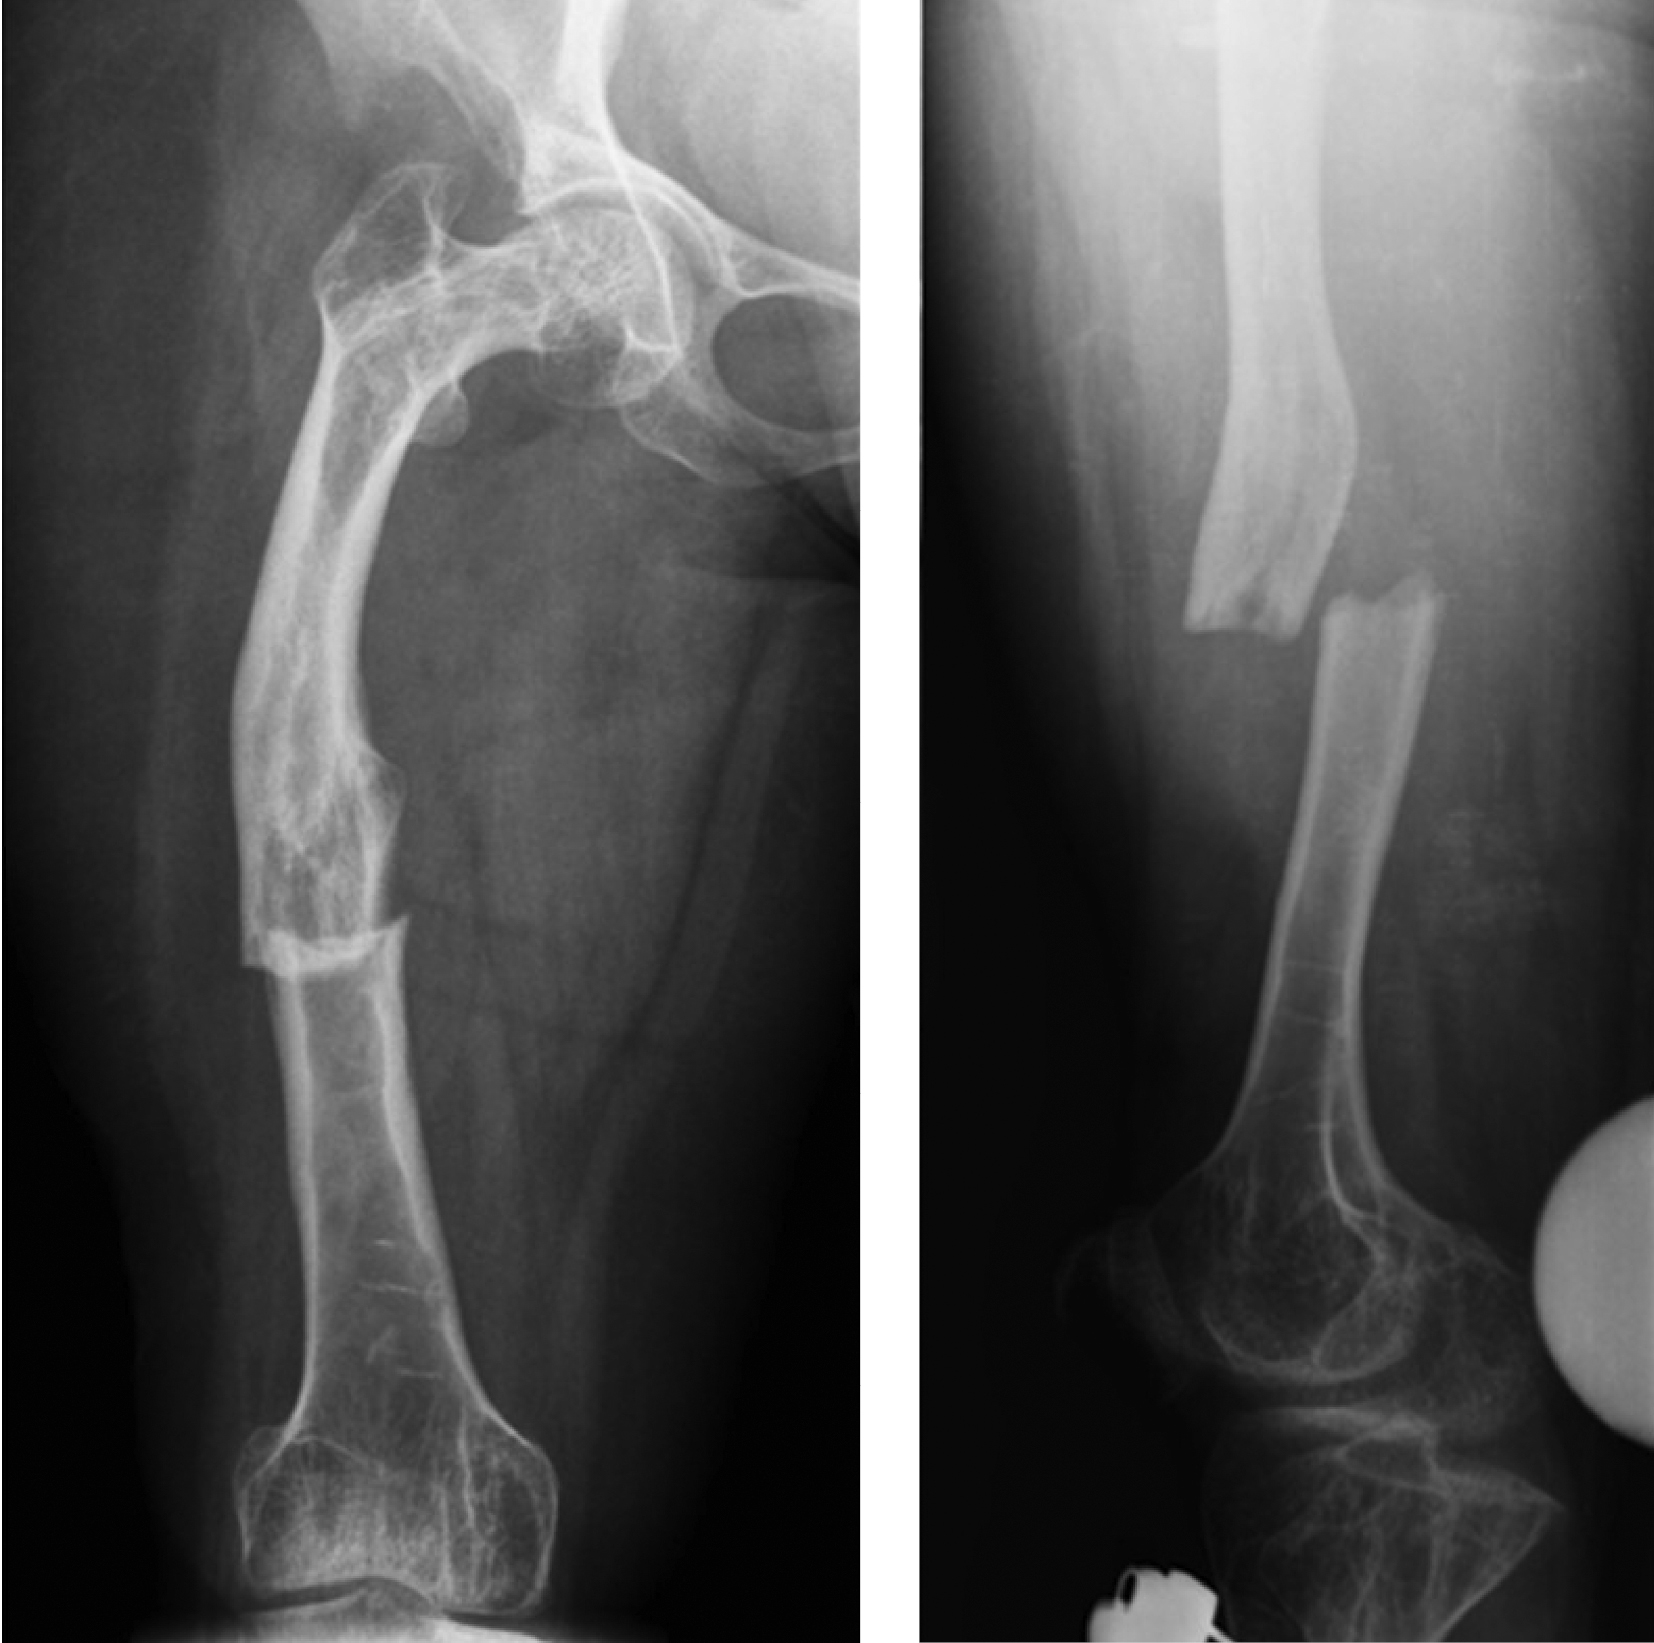

Несмотря на достигнутую консолидацию перелома проксимального отдела правой бедренной кости, рентгенологически прослеживается его зона, что характерно для НО (рис. 7). Ось оперированной бедренной кости близка к оси здоровой кости (рис. 8).

Рисунок 7. Рентгенограммы правой бедренной кости пациентки 5 лет и 4 месяца после оперативного вмешательства.

Рисунок 8. Осевые рентгенограммы нижних конечностей через 5 лет и 4 месяца после оперативного вмешательства на правом бедре.